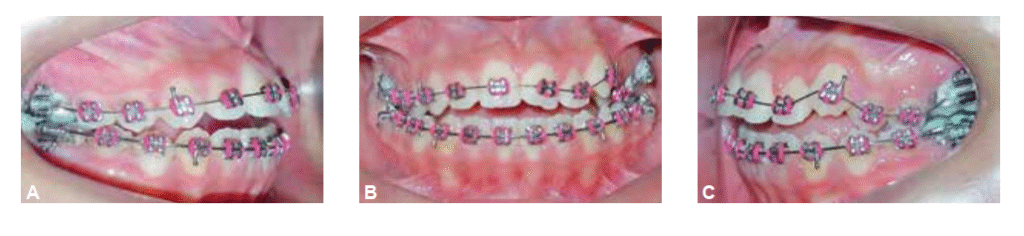

Foi realizado desgaste interproximal do esmalte dentário na região anteroinferior a fim de se conseguir a correção da discrepância entre os tamanhos dos dentes superiores e inferiores. Após o alinhamento foi inserido o elástico em cadeia de molar a molar nos arcos superior e inferior juntamente com o uso de elásticos de Classe III 3/16” de força média bilateralmente (Figura 7 A-C).

Após a remoção do aparelho fixo foi instalada como contenção uma placa de Hawley superior, 3×3 inferior e uso noturno de mentoneira com finalidade de restringir o crescimento mandibular. O tratamento proposto possibilitou a correção da discrepância transversal e da relação anteroposterior de forma satisfatória, melhorando o perímetro do arco e obtendo-se uma relação molar de Classe I (Figura 8 A-E), além da melhora significativa do perfil facial e estética mais agradável (Figura 9 A-B). As telerradiografias inicial e final mostram a melhora da relação entre as bases ósseas (Figura 10) juntamente com a sobreposição dos cefalogramas (Figura 11).